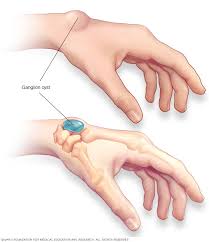

Una imagen como esta está circulando con fuerza en redes sociales: una pequeña protuberancia en la muñeca que aparece aparentemente de la nada. El mensaje es alarmante: “Este bulto puede aparecer por algo que haces todos los días”.

🧠 ¿Qué es ese bulto en la muñeca?

En la mayoría de los casos, este tipo de protuberancia corresponde a un quiste ganglionar, una masa benigna llena de líquido que se forma cerca de las articulaciones o tendones.

Es especialmente común en la muñeca y puede variar en tamaño.

Ese pequeño bulto en la muñeca puede parecer alarmante, pero en muchos casos es una condición benigna conocida como quiste ganglionar.